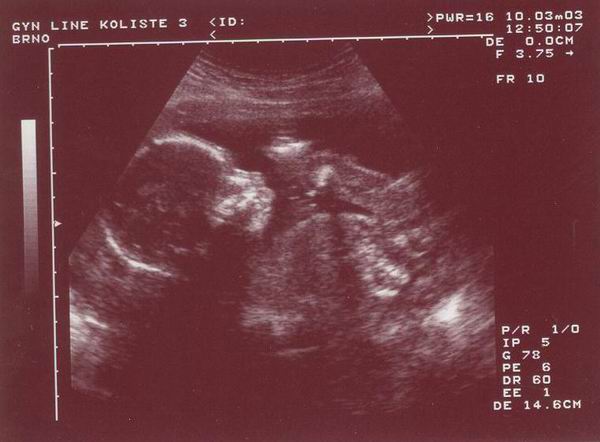

A takto jsem vypadal ve dvaceti týdnech.